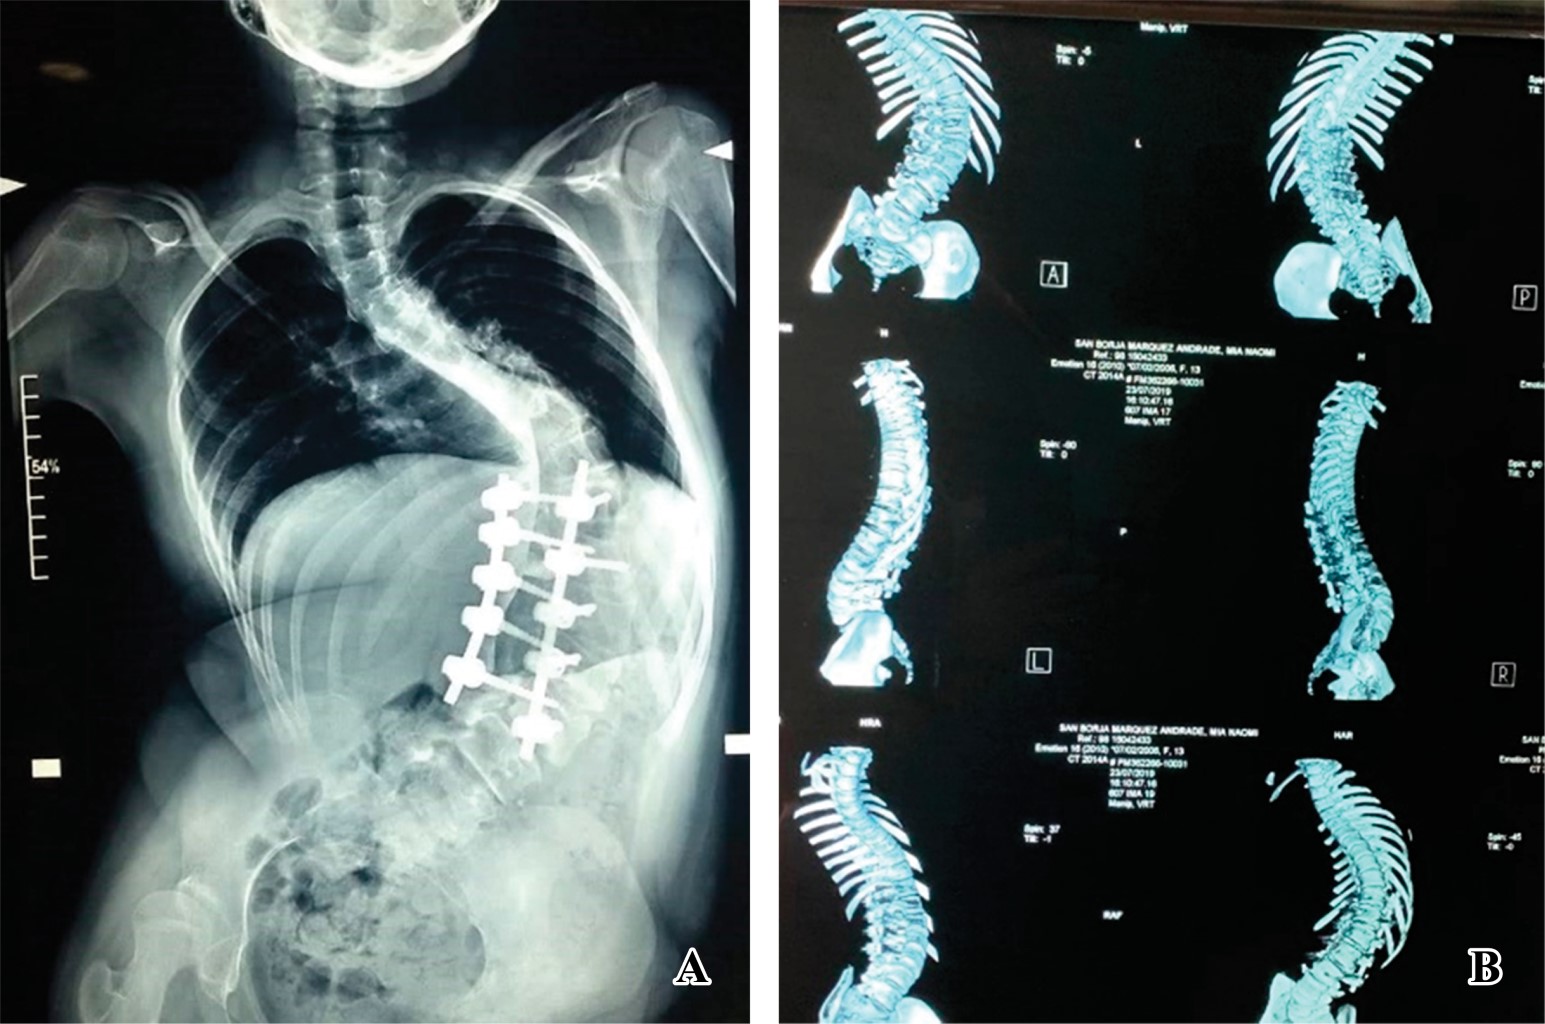

Introduction: Scoliosis is a complex deformity that affects all three planes of the axis of the spine. The association between neuromuscular pathology and vertebral alignment was initially described in 1960. Neuromuscular pathology is progressive and results in postural abnormalities. Surgical goals in patients with neuromuscular deformity include anatomical correction for sedation and ambulation, as well as functional improvement. The gold standard of treatment is by posterior approach with transpedicular screws. The "hands-free" technique saves surgical time, decreases radiation by reducing the use of fluoroscopy. The advent of 3D printing technology allows precise study of the anatomical area and detail of the deformity in its three planes. This model can be sterilized for transoperative guidance. A 13-year-old female patient who develops thoracolumbar neuromuscular scoliosis secondary to spastic cerebral palsy (CP), with previous instrumentation T11-L3 of which he develops severe proximal curve. After the segmentation of the three-dimensional model, pedicle violation greater than 2 mm towards bilateral medullary canal was detected in the pedicles of L1 and L2 of previous instrumentation, pedicle dysplasia and the morphological characteristics of the pedicles were observed. Three-dimensional planning and the use of surgical guides represent a tool for surgical planning, especially in severe cases and with pedicle dysplasia. It helps as a surgical guide for the placement of hands-free transpedicular screws with possible reduction of radiation and anesthetic time.

Figure 1

Figure 2